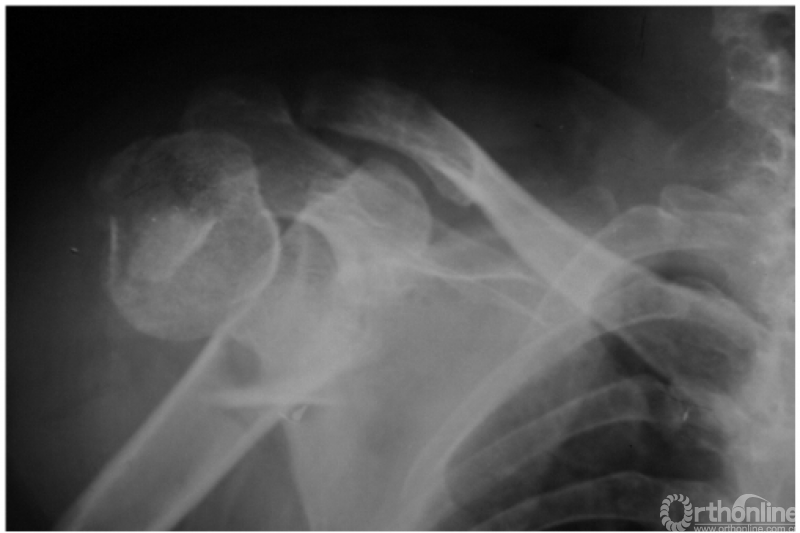

肩关节后脱位是所有大关节脱位中最易误诊的一种损伤,其误诊率可高达60%,因此该病有“诊断的陷阱”之称,有学者指出肱骨头关节面与盂前缘距离大于6mm时应高度怀疑有后脱位的可能。

此外,由于脱位后上臂外旋受限,因此即使在最大外旋位拍片时仍不能显示出肱骨颈及大结节的轮廓。例:肱骨头离开关节盂而向后外上方(肩峰之下)移位且内旋,致肱骨头与肱骨干在一直线上,招致肩肱曲线不流畅,肱骨头关节面与盂前缘距离大于6mm并小结节骨折(如下图)。